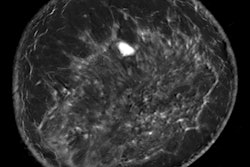

The French have a strong track record when it comes to the detection of pulmonary embolism (PE), as shown by the pioneering work of Prof. Martine Rémy-Jardin, PhD, from Lille and others. Researchers from the Hôpital de la Cavale Blanche in Brest have published an important study this week on the use of CT pulmonary angiography in PE, and you won't want to miss it. Learn more in the CT Community.